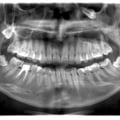

Лікування карієсу дистопованого 48 зуба не є вирішенням даної патології. Дистопія зуба мудрості провокує виникнення карієсу 47 зуба. Даний зуб має бути видалений